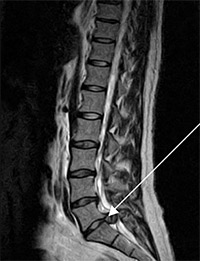

Εικ 3.

Μαγνητική τομογραφία: μεγάλη οσφυοϊερή δισκοκήλη